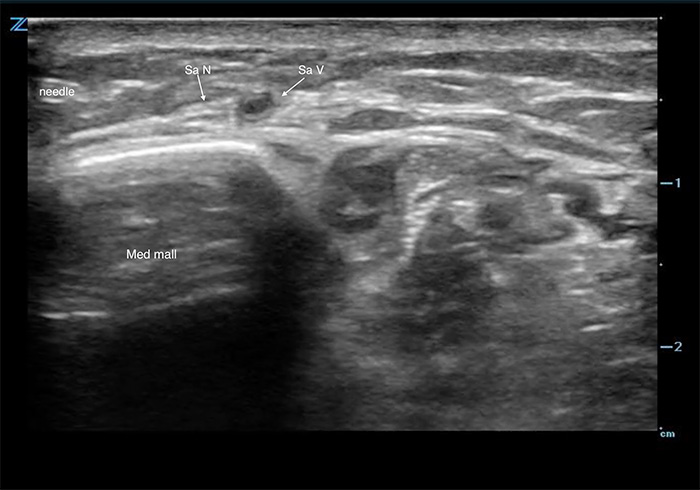

- A high-frequency linear array probe is applied in a transverse plane anterior to the medial malleolus.

- Identify the greater saphenous vein anterior and superficial to the medial malleolus.

- The vein will collapse easily in most patients, so a tourniquet placed around the calf and light probe pressure are likely required.

- The small, echogenic saphenous nerve may be identified adjacent to the vein in any orientation, but it is commonly very difficult to see.

- If the nerve is not apparent, tracing the vein proximally may highlight the hyperechoic nerve following the vein.

- If the nerve is still not visualized, the saphenous vein is used as the target for injection.

Figure 1. Saphenous nerve